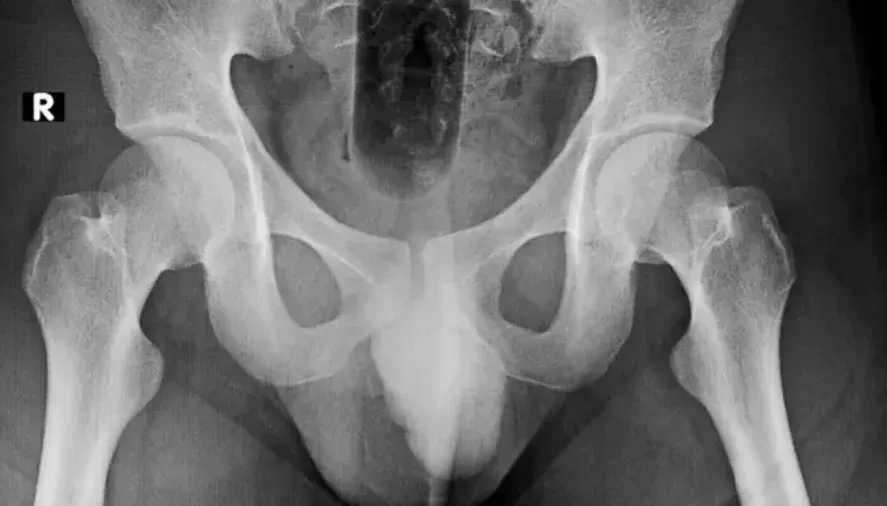

ชายรายดังกล่าวเข้ามาพบแพทย์ โดยมีอาการปวดอย่างรุนแรงบริเวณก้น เขายอมรับว่าได้สอดใส่วัตถุบางอย่างเข้าไปในร่างกาย แต่ไม่ได้ระบุรายละเอียดว่าวัตถุนั้นคืออะไร... ภายหลังจากการผ่าตัด แพทย์จึงพบว่าวัตถุดังกล่าว คือ กระสุนปืนใหญ่ขนาดประมาณ 16x4 เซนติเมตร ซึ่งเป็นอาวุธจากสงครามโลกครั้งที่ 1 [ประมาณปี 1918]